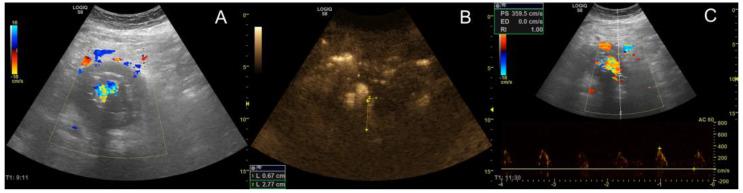

Endoleaks are the most common complication after endovascular aortic repair (EVAR). Their correct identification is one of the main objectives of surveillance protocols after EVAR. So far, computed tomography angiography (CTA), contrast-enhanced (CEUS) and Duplex ultrasound (DUS), as well as magnetic resonance angiography, have been investigated for their ability to detect endoleaks. In general, all technologies have distinct benefits and disadvantages, with CTA and CEUS emerging as the reference standard for surveillance after EVAR. However, they are both contrast-enhancer-dependent, and CTA additionally exposes patients to ionizing radiation. In the present study, we investigated B-Flow, a type of coded-excitation ultrasound that was specifically designed to optimize the visualization of blood flow, for its ability to detect endoleaks, and compared its performance to CEUS, CTA, and DUS. In total, 34 patients were included in the analysis that accumulated in 43 distinct B-Flow investigations. They underwent a total of 132 imaging investigations. Agreement between B-Flow and other imaging modalities was high (>80.0%), while inter-method reliability can be interpreted as good. However, with B-Flow, six and one endoleaks would have been missed compared to CEUS and CTA, respectively. Regarding endoleak classification, all metrics were lower but retained an adequate level of comparison. In a subset of patients requiring intervention, B-Flow had 100% accuracy regarding both endoleak detection and classification. Ultrasonography enables endoleak detection and classification without the need for pharmaceutical contrast enhancement or radiation. Ultrasound coded-excitation imaging in the application of B-Flow could further simplify surveillance after EVAR by offering adequate accuracy without requiring intravenous contrast enhancement. Our findings may promote subsequent investigations of coded-excitation imaging for endoleak detection and classification in the surveillance after EVAR.

内漏是血管腔内主动脉修复术(EVAR)后最常见的并发症。正确识别内漏是EVAR术后监测方案的主要目标之一。到目前为止,计算机断层血管造影(CTA)、对比增强超声(CEUS)和双功超声(DUS)以及磁共振血管造影都已被研究用于检测内漏的能力。一般来说,所有技术都有明显的优缺点,CTA和CEUS已成为EVAR术后监测的参考标准。然而,它们都依赖于对比剂增强,而且CTA还会使患者暴露于电离辐射中。在本研究中,我们研究了B-Flow,一种专门设计用于优化血流可视化的编码激励超声,以检测其检测内漏的能力,并将其性能与CEUS、CTA和DUS进行比较。总共34例患者纳入分析,累积进行了43次不同的B-Flow检查。他们总共接受了132次成像检查。B-Flow与其他成像方式之间的一致性很高(>80.0%),而方法间的可靠性可解释为良好。然而,与CEUS和CTA相比,使用B-Flow分别会漏诊6例和1例内漏。关于内漏分类,所有指标都较低,但仍保持了足够的比较水平。在一部分需要干预的患者中,B-Flow在内漏检测和分类方面的准确率均为100%。超声检查能够检测和分类内漏,而无需药物对比增强或辐射。在B-Flow应用中进行超声编码激励成像,无需静脉注射对比剂增强即可提供足够的准确性,从而可进一步简化EVAR术后的监测。我们的研究结果可能会促进后续关于编码激励成像在EVAR术后监测中检测和分类内漏的研究。